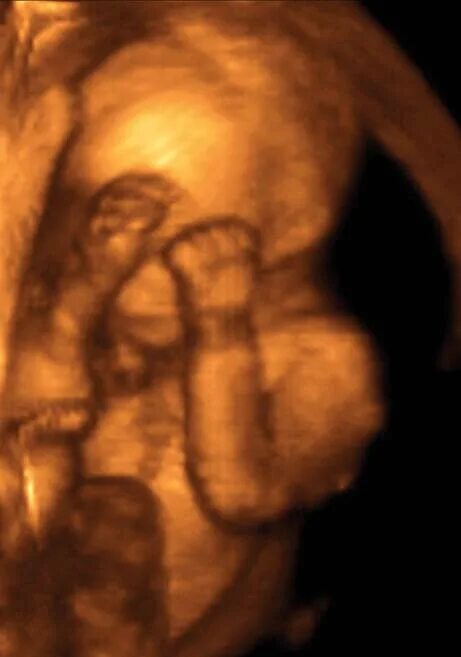

20 недель часто шевелится